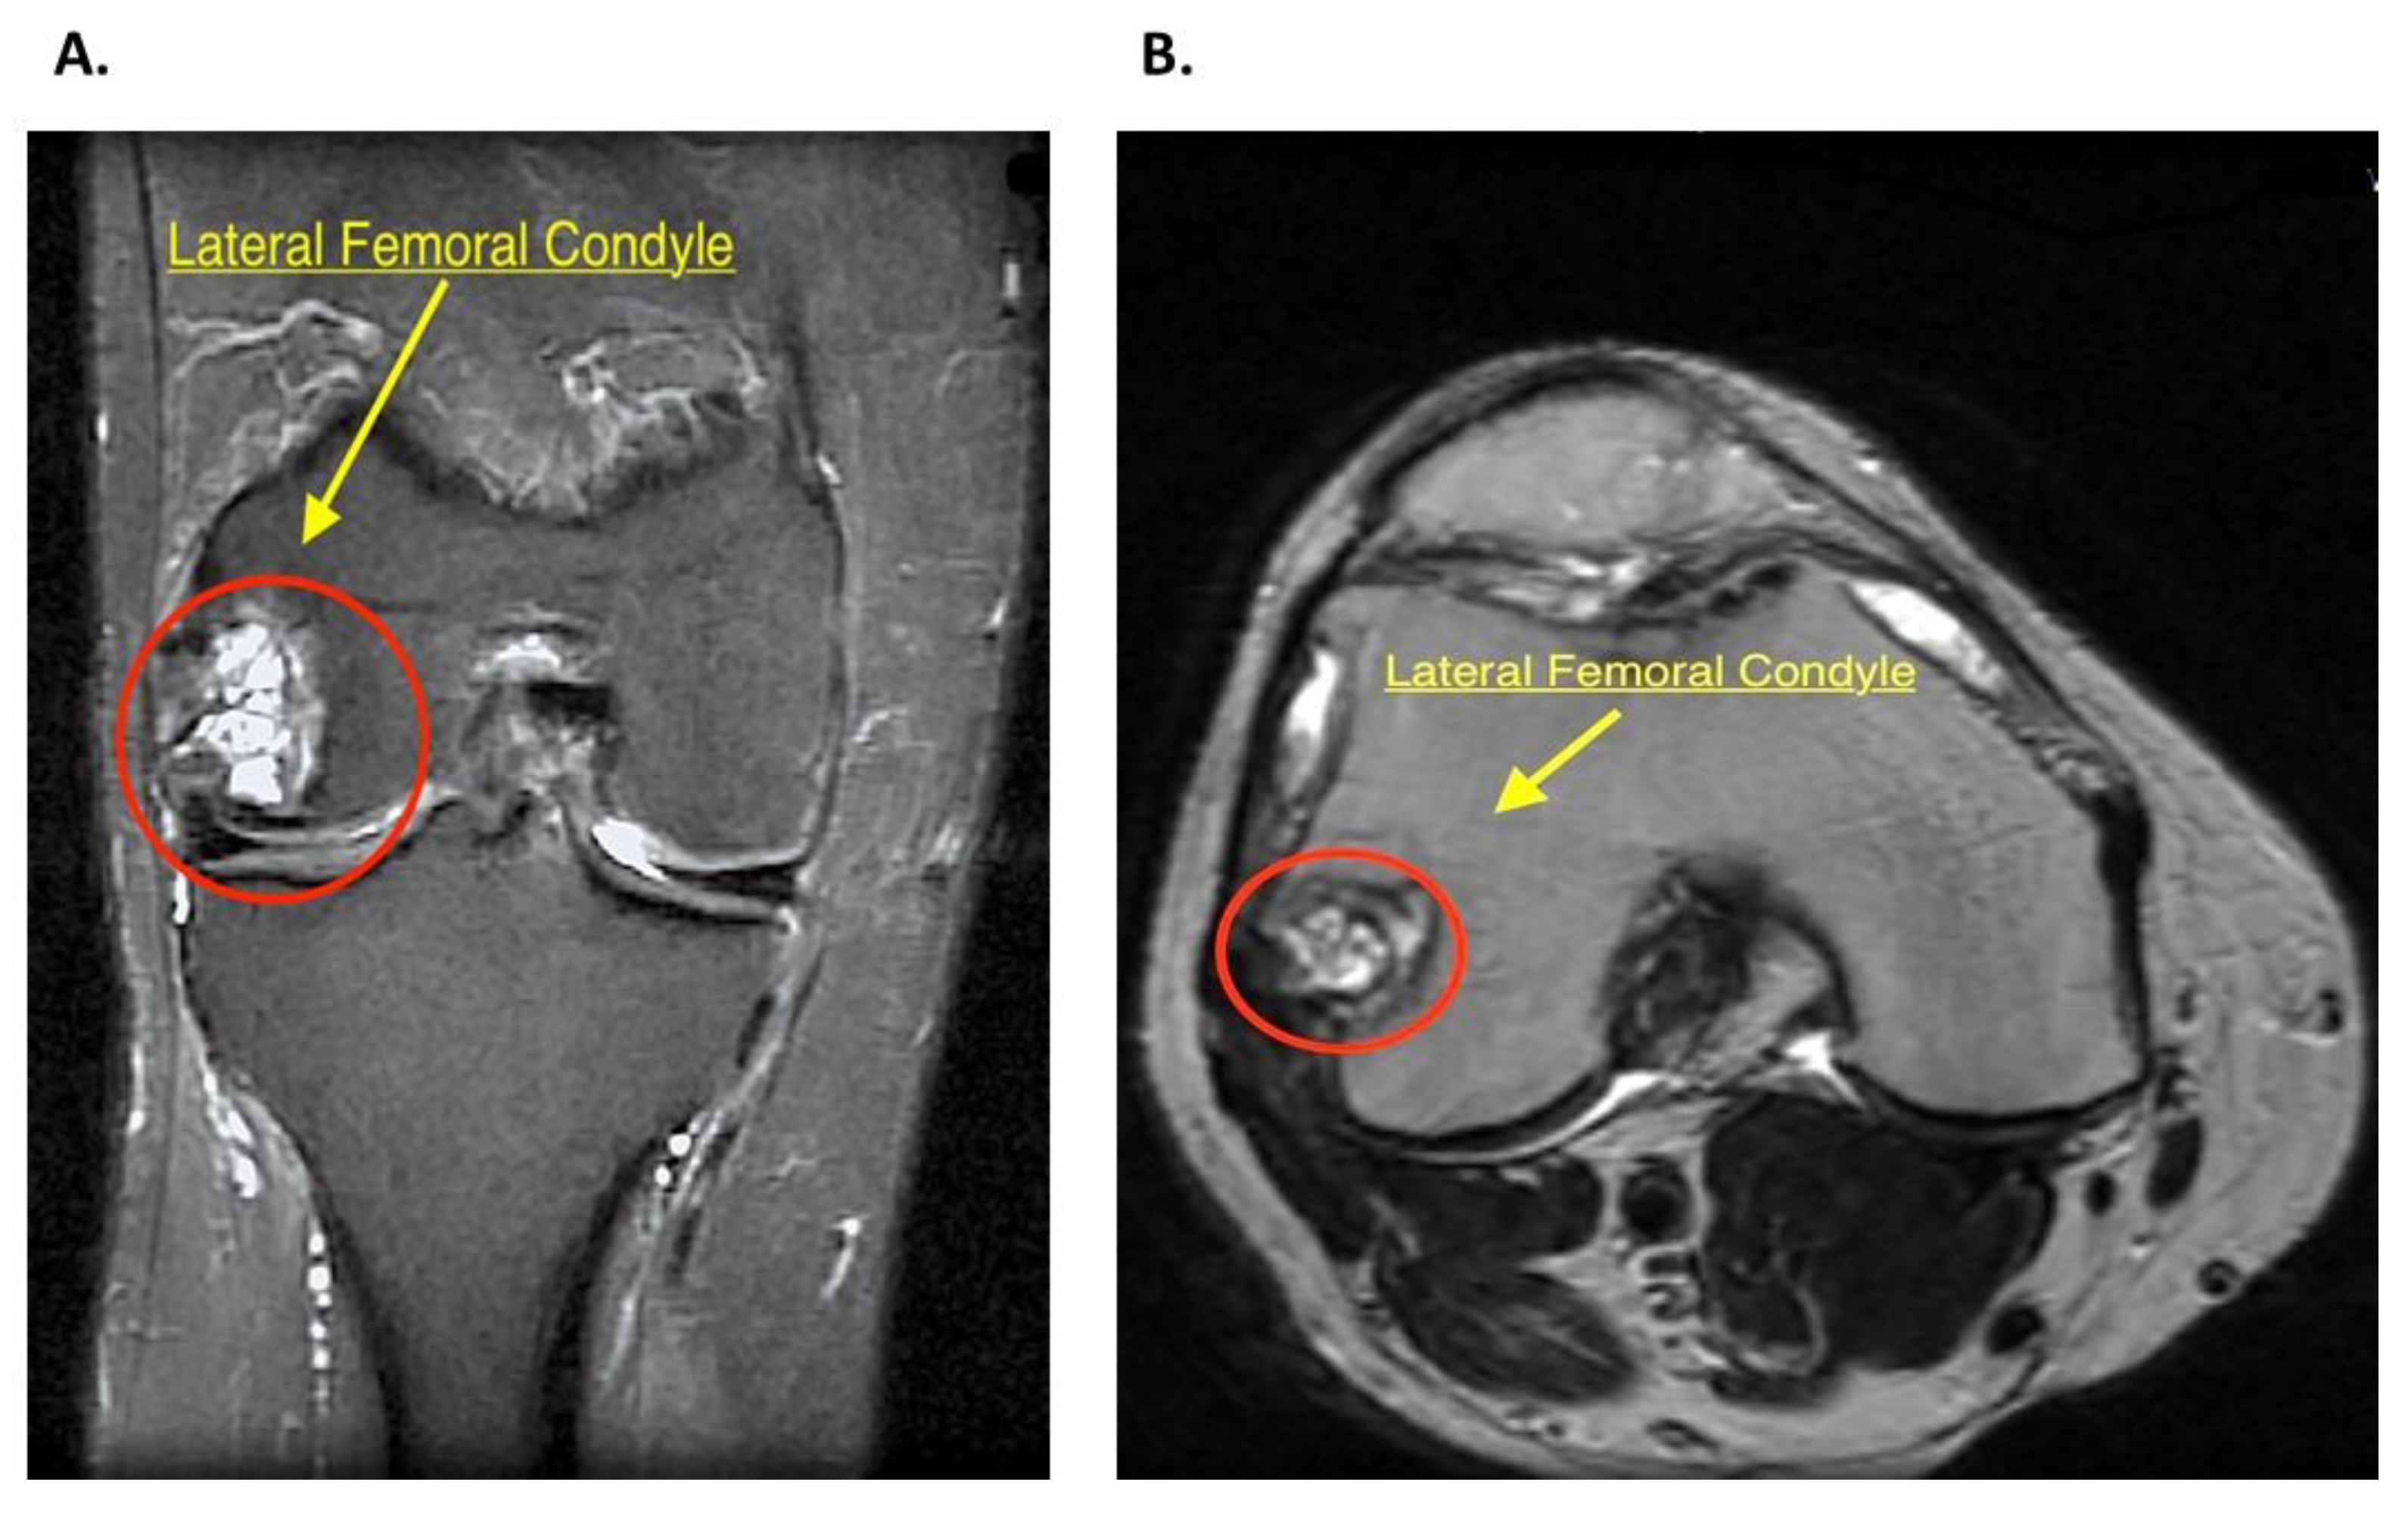

Intraosseous Bioplasty for a Subchondral Cyst in the Lateral Condyle of Femur

2.2. History and Diagnosis